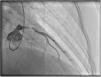

A repeat coronary angiography was performed, which showed a thrombosis in myocardial infarction (TIMI 2) subocclusive lesion in the anterior descending artery (90–99%). Here an anti-proliferative drug-coated stent (BioMatrix Flex 3.5×14 mm) was placed with a TIMI 3 final result (Figure 3). During the procedure, aortography was performed, which did not reveal any suspect image of aortic dissection.